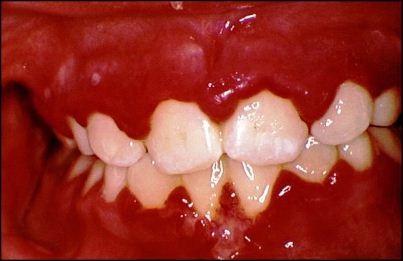

Разрастание десневой ткани, характерное для третьей степени, достигает критических размеров, десневой край нависает над жевательной поверхностью зубов и их режущим краем. Изменяется рельеф десны, нарушается ее целостность. Поверхность десны покрывается кровоточащими грануляциями, которые очень болезненны и могут гноиться. Межзубные сосочки существенно увеличиваются в размерах и приобретают овальную форму.

Гранулирующая форма, сопровождающаяся исчезновением эпителия в области зубодесневых сосочков и десневого края, называется десквамативным гингивитом. Характерным признаком десквамативного гингивита является обнажение слизистой десен. При визуальном осмотре пациента пораженные участки имеют вид ярко-красных углублений. Обнаженные участки отличаются высокой болезненностью, что затрудняет процесс жевания. Кровоточивость возникает внезапно, больной ощущает постоянное чувство жжения десен в области очагов поражения.